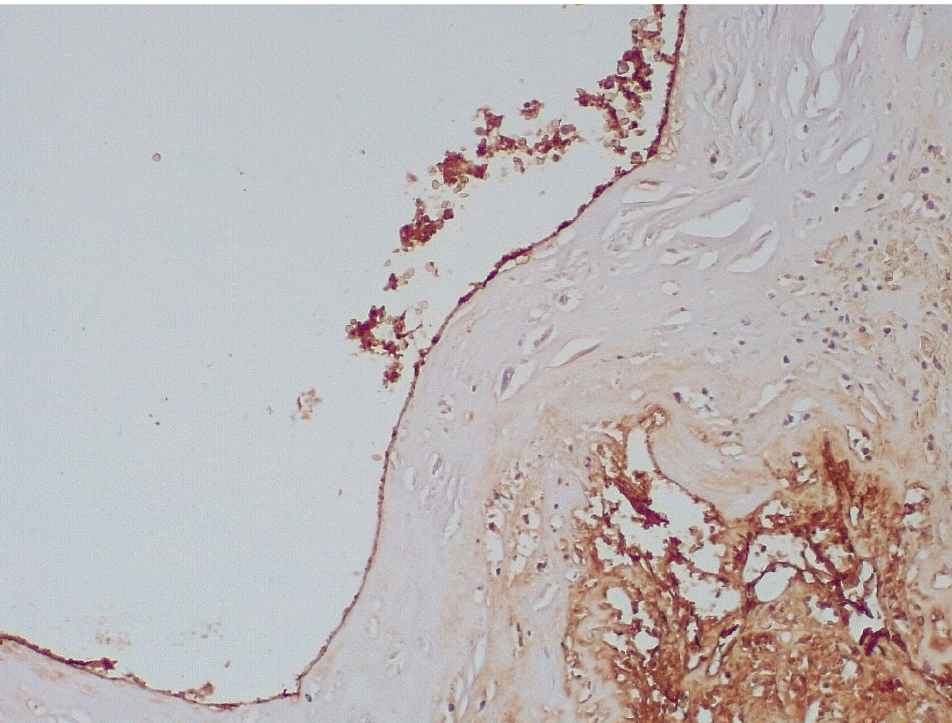

В течение 7–15 суток после стентирования КА наряду с формированием пристеночных фибриновых тромбов с признаками организации в стенках атером наблюдались репаративные процессы, связанные с неоангиогенезом в виде образования мелких тонкостенных кровеносных сосудов капиллярного типа, окруженных мелкими лимфоцитарными, гистиоцитарными клеточными инфильтратами (рис. 6, 7).

Сохранялась резковыраженная яркая экспрессия ФВ как со стороны интимы, так и субинтимально, в участках альтерации атером (рис. 8). В то же время экспрессия белка CD31 была негативной на всем протяжении стенок КА.